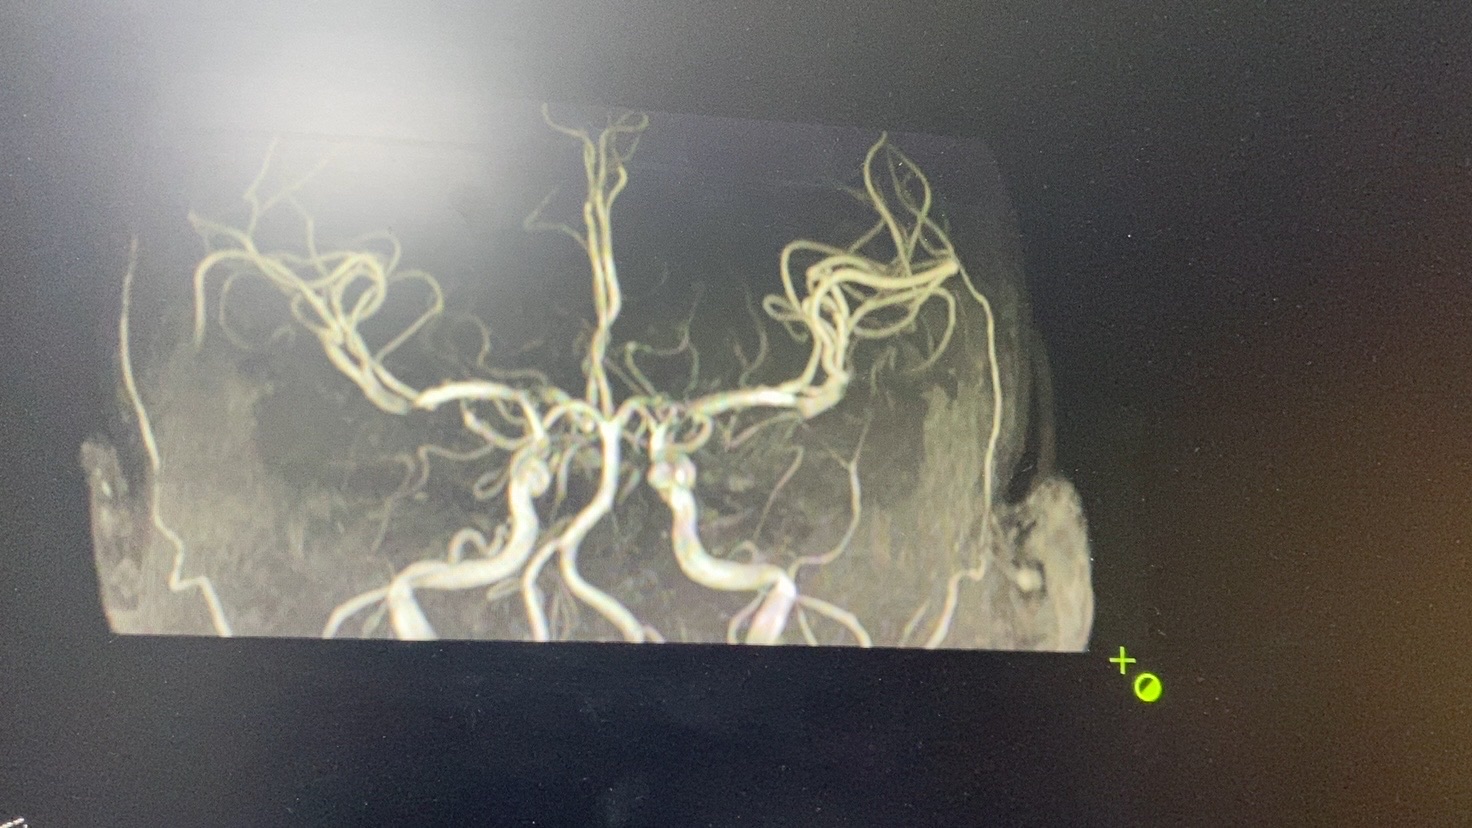

头MRA